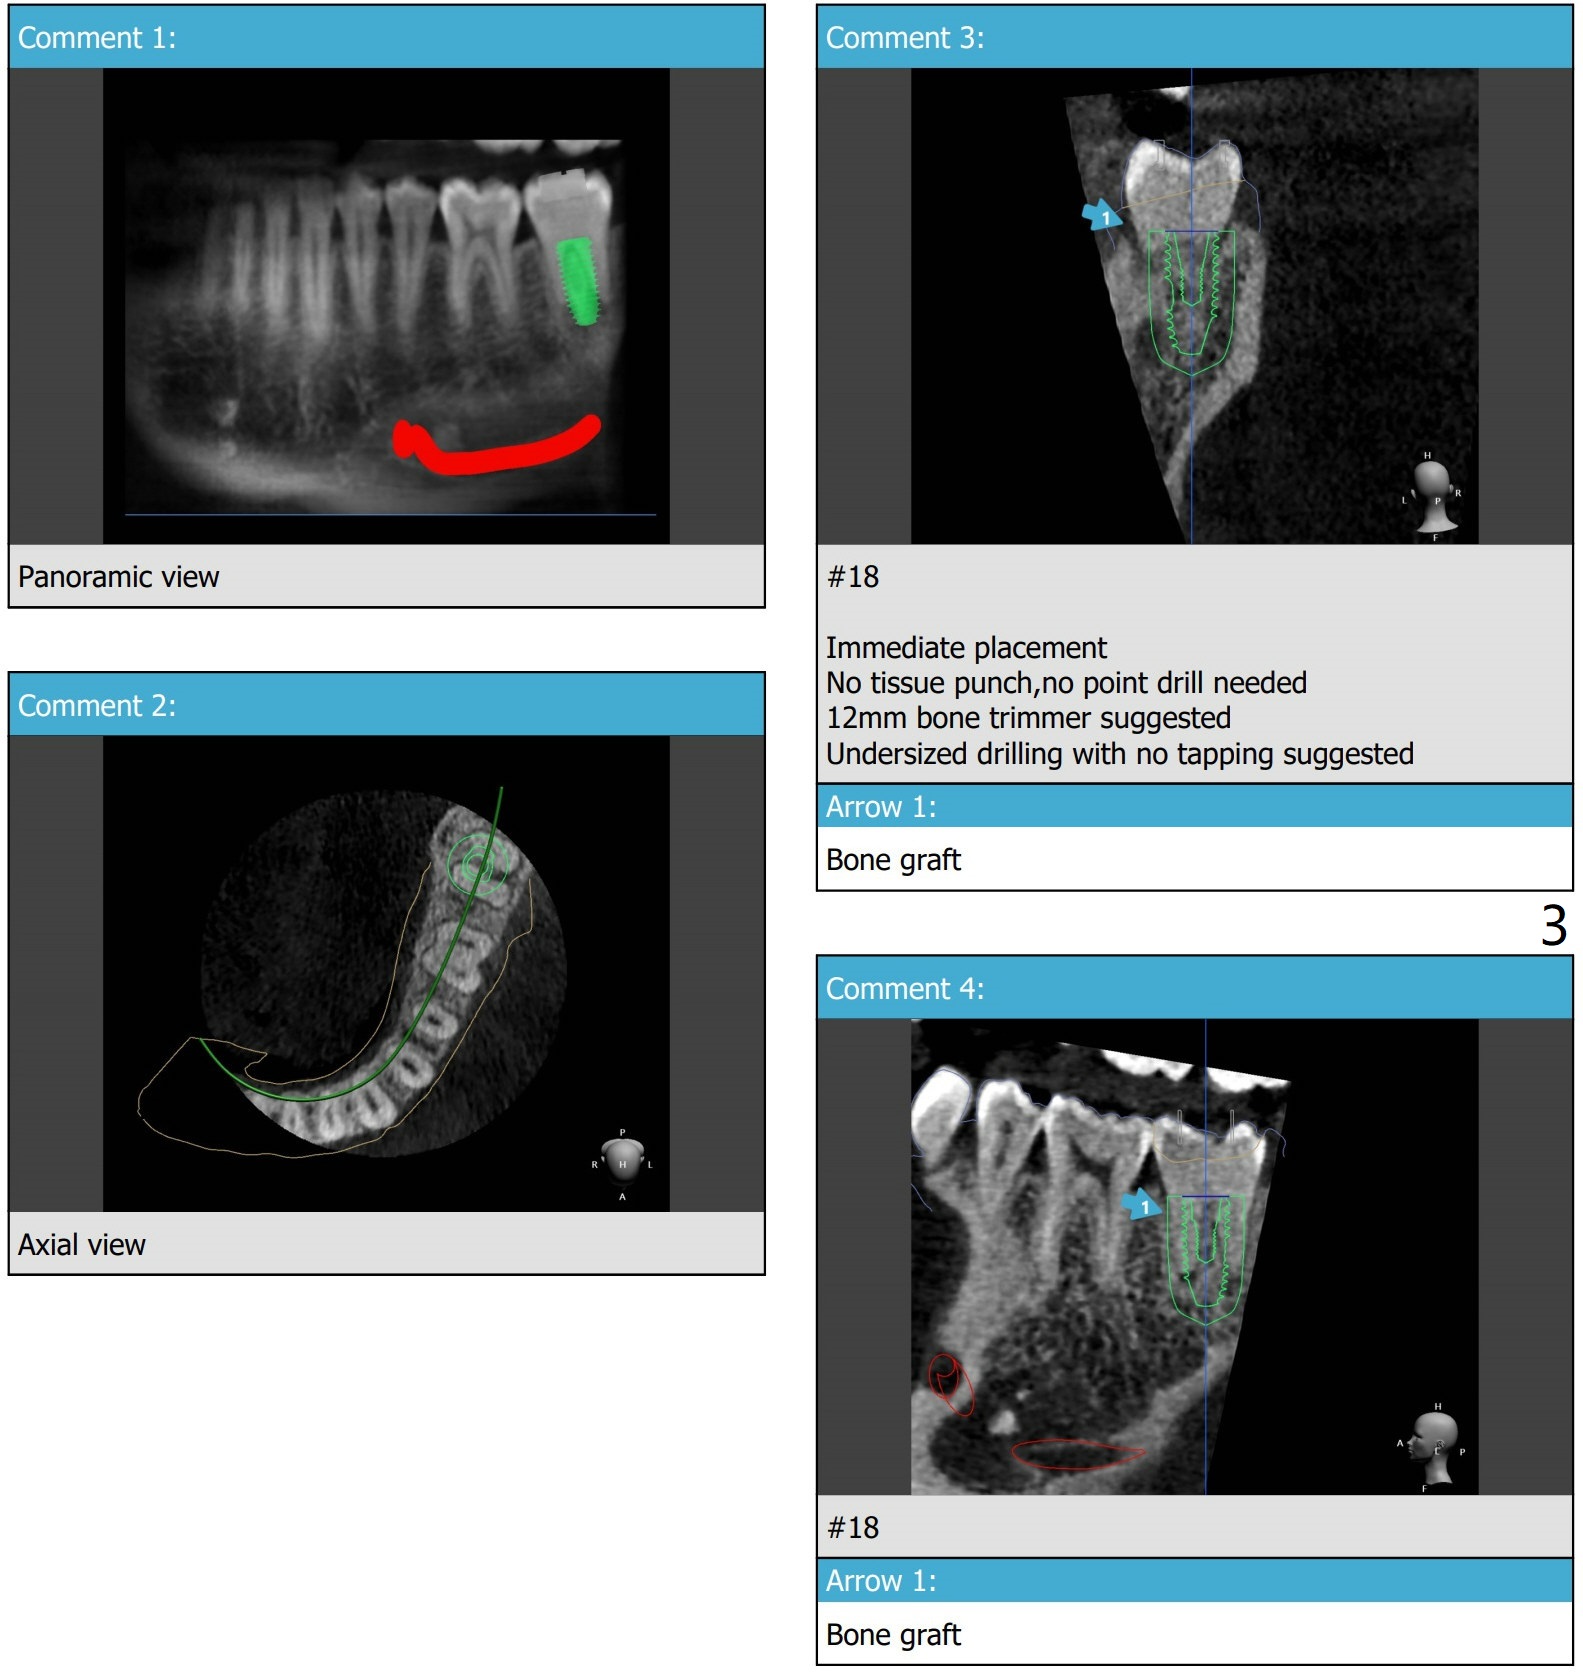

Long Implant Relative to Guide

Prepare the adult bite block for long drill and implant. Section off the crown, keep the roots for osteotomy. Use a short (trimmed) temporary abutment to keep bone graft in place securely. Return to No Caries 植牙,导板与正畸 Xin Wei, DDS, PhD, MS 1st edition 11/05/2020, last revision 01/10/2021